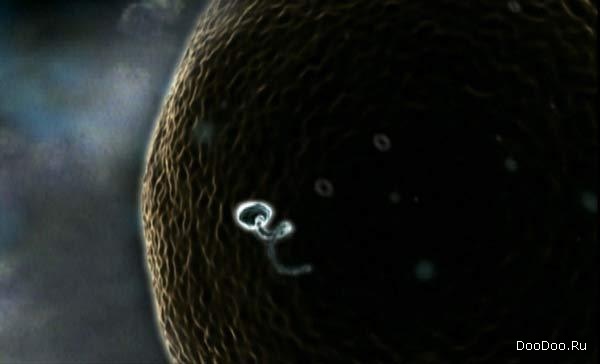

Первая неделя. Человеком пока еще и не пахнет.